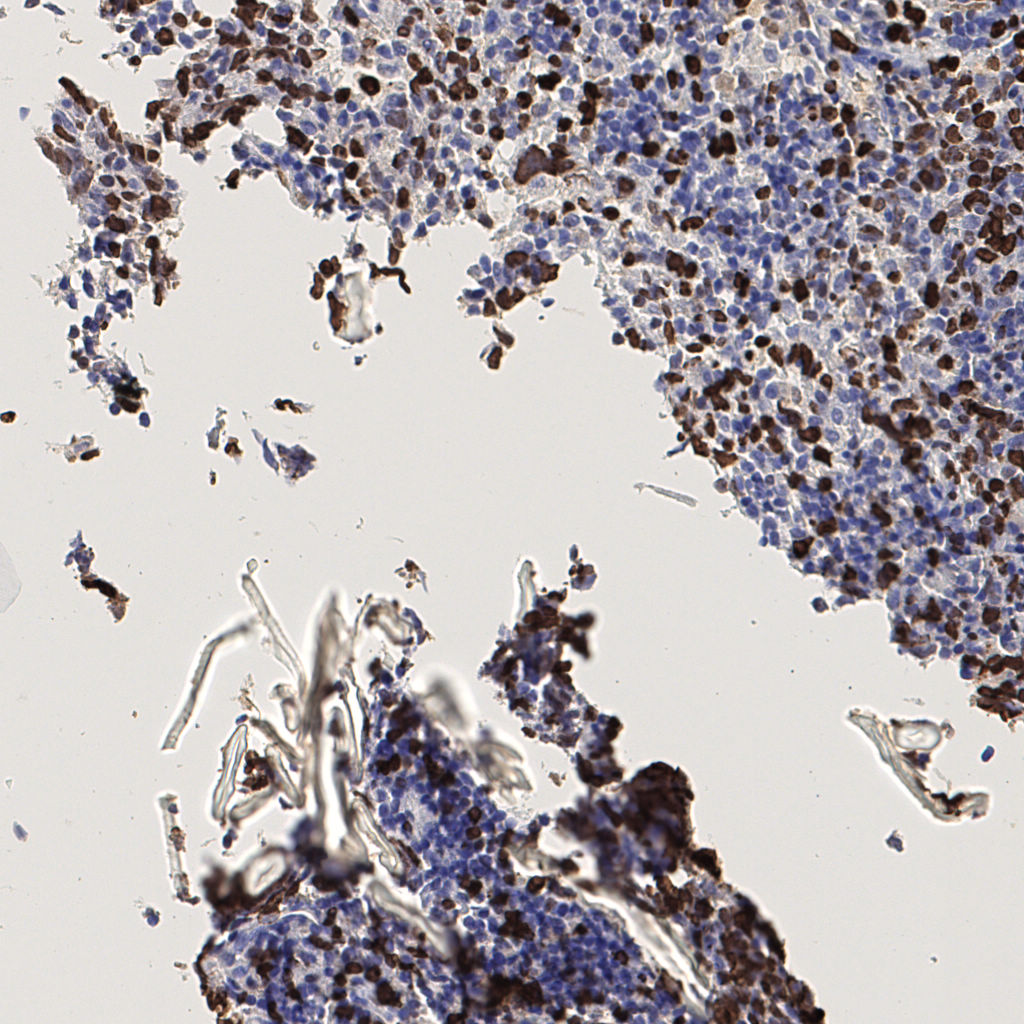

7.85%

Ki67 指数

阴 1104 阳 94